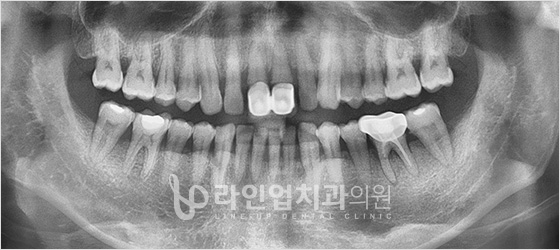

Before

After

Имплантация передних зубов